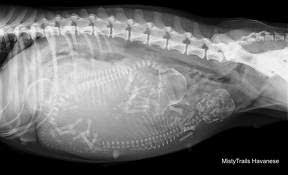

Para usar a calculadora de gravidez deve ser levado em conta como início o primeiro dia da última menstruaçãoA partir daí sabe-se que podem ser 39 40 ou 41 semanas até o bebê nascer a termo no tempo certo. A gestação canina dura entre 58 e 68 dias em média de 60 a 63 dias e os primeiros sinais começam a se manifestar por volta do 20º dia. Os filhotes de yorkshire terrier costumam ter a pelagem marrom preta e castanha mas quando crescem exibem lindos tons de preto e dourado preto e castanho azul aço e dourado ou azul aço e castanho.